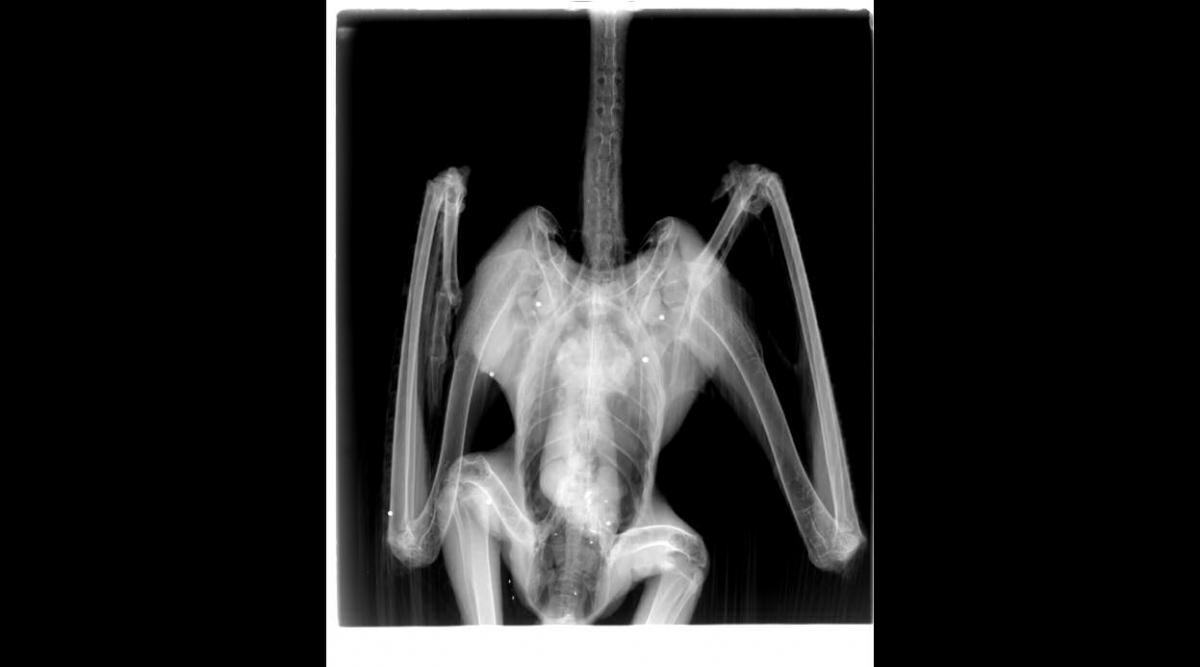

zestřelený

o zásahu broky orli hynou buďto přímo nebo později na následky zranění. Někdy mají ptáci štěstí a broky se v těle zapouzdří a nezpůsobují žádné další problémy. Střílení dopadá na všechny věkové skupiny, od vajec v hnízdě po dospělé. Zhodnotit významnost tohoto typu pronásledování je těžké, ale může k němu docházet na hnízdištních, lovištích i zimovištích v průběhu celého roku